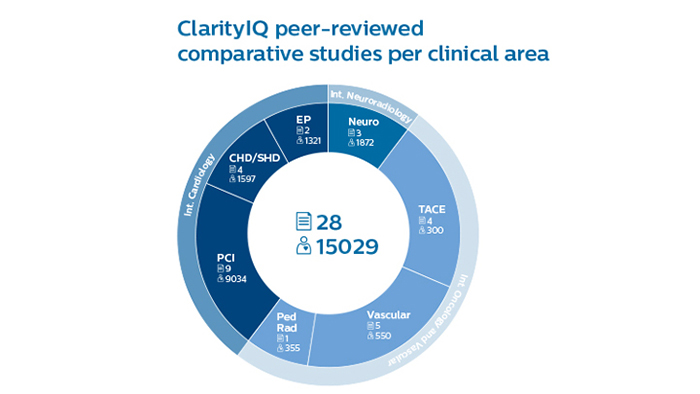

鮮明な画像を低線量で実現

ClarityIQテクノロジーは、ClarityIQを使用しないシステムと比較した場合、同等の画質を維持しながらDSAでの患者線量を75%削減します¹。リアルタイム体動補正により、頭蓋骨および体動アーチファクトが除去されます。これは、頭蓋骨の底部にデバイスを留置する際に重要です。